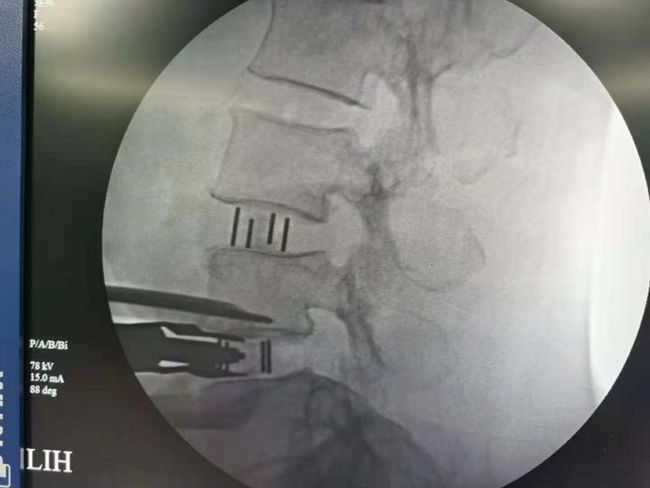

OLIF手术

椎间隙撑开后达到间接减压的目的

OLIF微创手术是目前流行的一种微创椎间融合手术,通过撑开椎间隙达到间接减压的目的。手术从腰部斜前侧方入路,从自然间隙到达腰椎,椎间处理后椎间隙撑开,做一个滑脱的复位,然后再根据患者情况I期或II期后路置入钉棒固定。

本病例患者L3/4存在腰椎滑脱、椎间隙高度丢失;但L4/5椎间隙高度丢失不明显,所以选择了L3/4、L4/5两个节段的OLIF同是进行L4/5的内镜手术(OLIF+内镜),充分的结合了两种术式的优缺点,是间接减压与直接减压的完美结合。所以对于严重的椎管狭窄或滑脱也是可以采用微创的方式来解决的。目前国内开展此类微创手术鲜有报道。